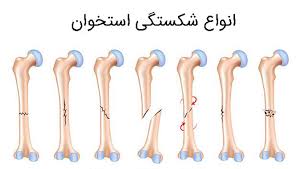

قیمت: 35٬000 تومان - دسته بندی فایل: پاورپوینتپاورپوینت بیماری های اسکلتی عضلانی پوکی استخوان (ppt) 24 اسلاید

فروش ویژه پاورپوینت حرفه ای بیماری های اسکلتی عضلانی پوکی استخوان / تعداد اسلاید : 24 اسلاید

قیمت: 96٬000 تومان - دسته بندی فایل: پاورپوینتپاورپوینت بیماریهای داخلی جراحی (ارتوپدی) (ppt) 218 اسلاید

فروش ویژه پاورپوینت حرفه ای بیماریهای داخلی جراحی (ارتوپدی) / تعداد اسلاید: 218 اسلاید

قیمت: 96٬000 تومان - دسته بندی فایل: پاورپوینتپاورپوینت استخوان بازو (ppt) 143 اسلاید

فروش ویژه پاورپوینت حرفه ای استخوان بازو / تعداد اسلاید: 143 اسلاید